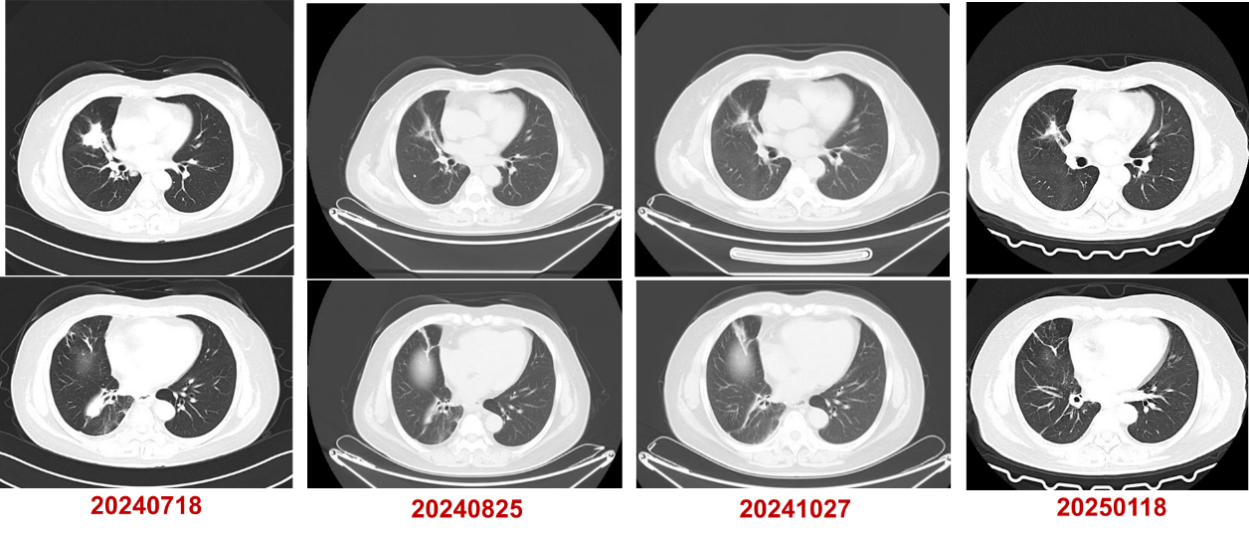

2024年7月至2025年4月,行长春瑞滨软胶囊(40mg,每周一、三、五)口服治疗。

疗效评估:PR。

基于上述证据并尊重患者意愿,本例患者三线采用口服长春瑞滨节拍化疗,疗效评估达到PR。截至末次随访时间(2025年4月),患者连续用药9个月余,无明显不良反应,疾病控制稳定,初步实现晚期肺癌的长期慢病化管理。